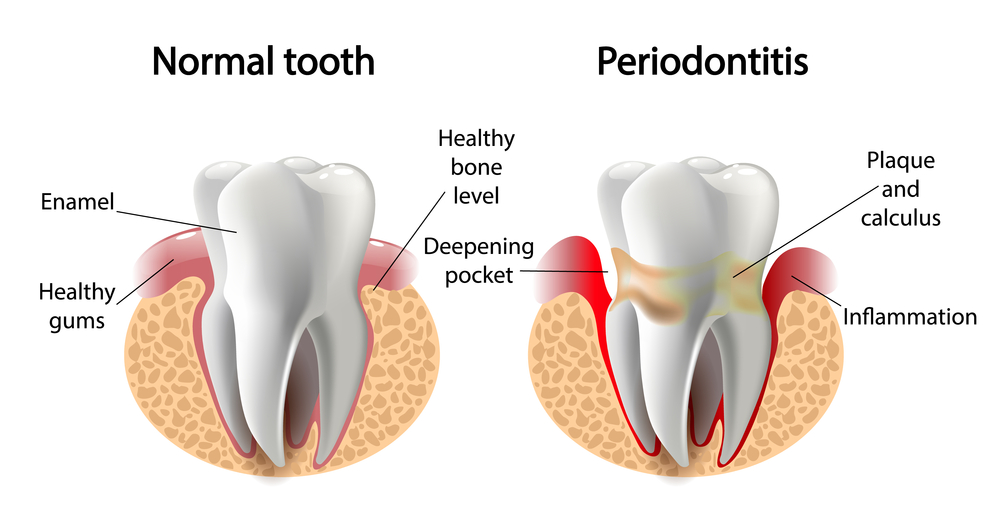

Gum disease is usually caused by severe plaque buildup and bacteria entering the gums, inflaming them. Without proper care, gum disease, otherwise known as gingivitis,

One of the most common symptoms of periodontal disease is gum recession. This occurs when the gum tissue begins to pull back from the teeth,

Treating gum disease at your periodontist in Ft. Lauderdale, FL, has often involved gum surgery in the past. If gum disease, also known as periodontitis,

Gum disease is quite common among adults in the United States. In fact, it is so common that many people may not think it is

We all know that gum disease can lead to gum recession and loose teeth but there is more to it than that. Gum disease not